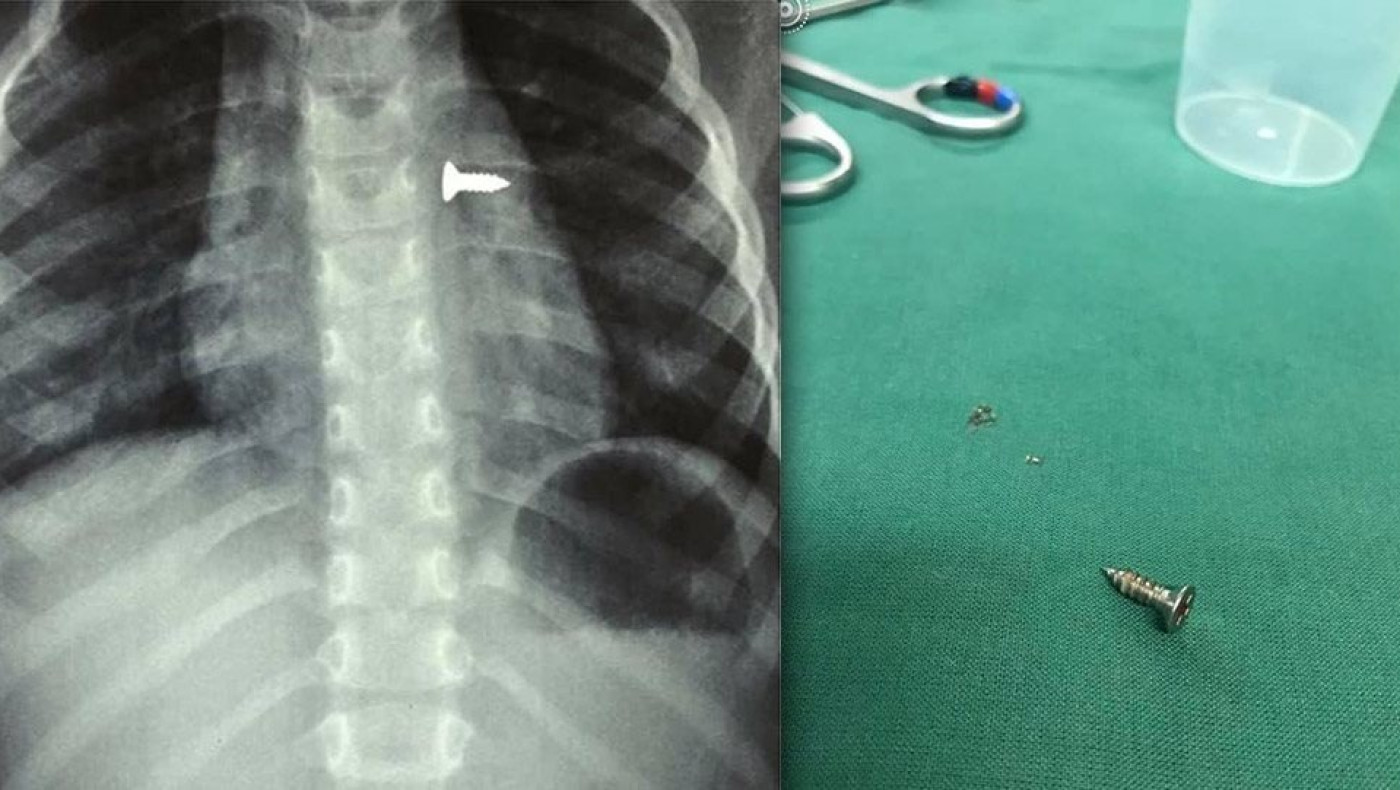

Κρήτη: Τρίχρονο κοριτσάκι κατάπιε βίδα που κατέληξε στον πνεύμονά του

Σοκάρουν οι ακτινογραφίες από ένα κοριτσάκι στην Κρήτη που κατάπιε βίδα, η οποία κατέληξε στον αριστερό του πνεύμονα.

Αμέσως έβγαλε ακτινογραφίες, που έδειξαν πως η βίδα βρισκόταν στον αριστερό του πνεύμονα.

Οι γιατροί οδήγησαν το κορίτσι στο χειρουργείο και μετά από αρκετή ώρα κατάφεραν να αφαιρέσουν την βίδα.

Ο κ. Προκοπάκης σε ανάρτησή του στα social media ανέφερε: «Πολύ επείγον χειρουργείο! Πριν από λίγο. Αφαίρεση βίδας από αριστερό βρογχικό δέντρο τρίχρονου κοριτσιού. Πολύ επικίνδυνο…».